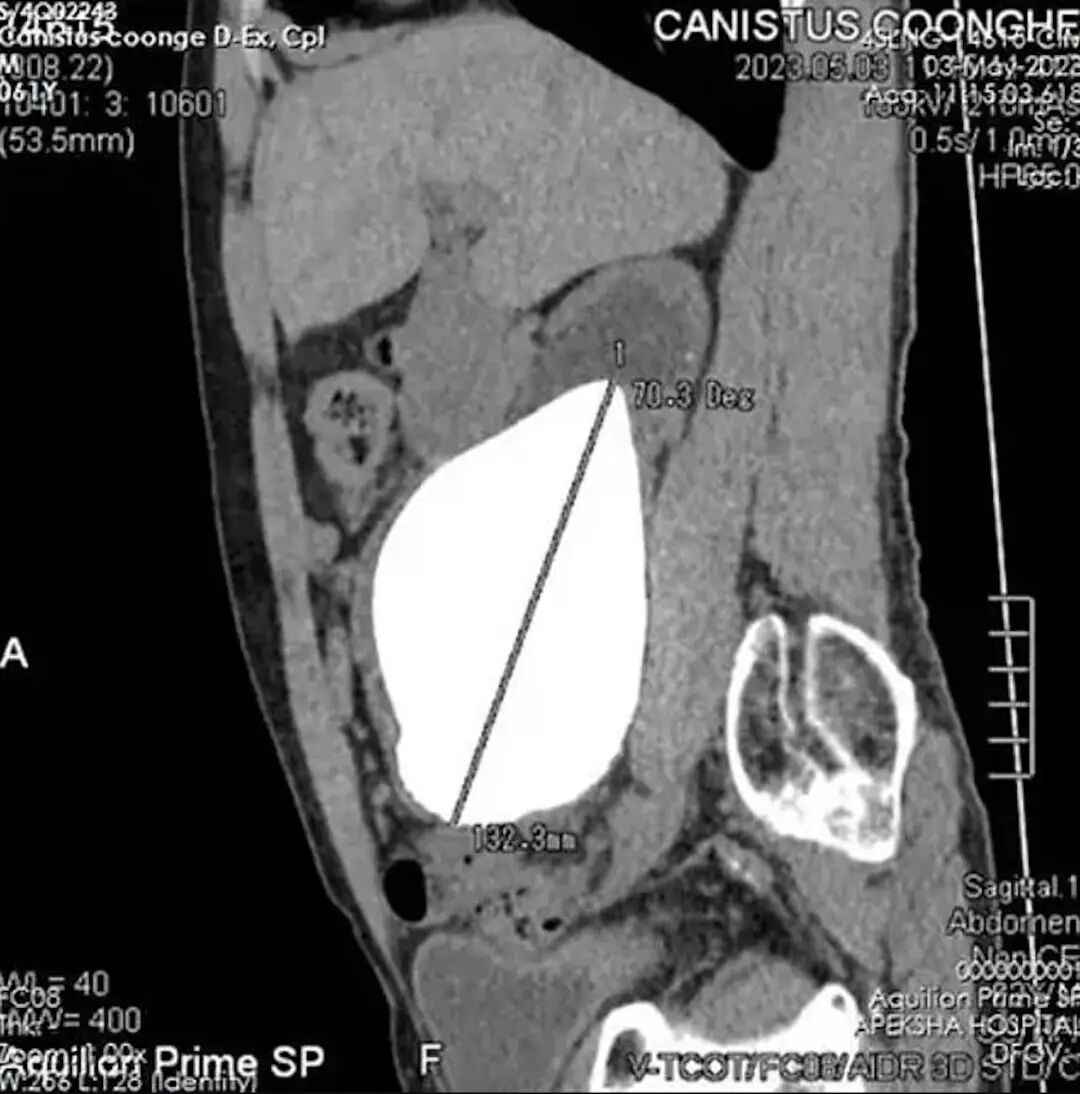

近日,一名来自斯里兰卡62岁的退役老兵经手术将体内的肾结石取出,这颗肾结石长约13.372厘米、重达801克,是有纪录以来全球最大最重,其大小更打破健力士世界纪录。肾结石是常见都市病,在30至60岁人士患症的情况尤其普遍,大约每10人就有1个人患有肾结石,到底肾结石是如何形成?想要预防又可以点做?